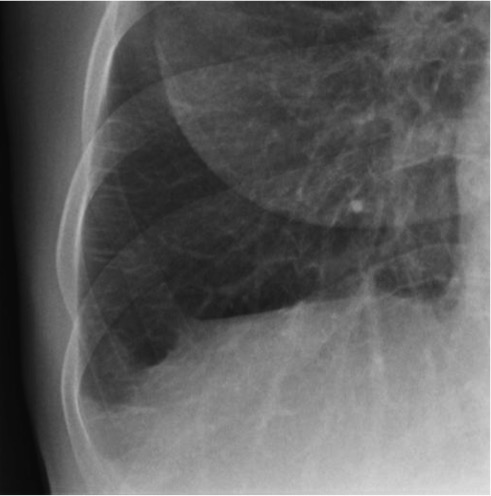

CASO: Febrícula y tos de 4 días de evolución.

Hallazgos:

- En la placa PA se observa una asimetría en los hilios pulmonares, el hilio izquierdo tiene una densidad aumentada.

- Tras examinar la placa lateral se observa un aumento de densidad en la columna que puede ser compatible con una condensación, es el signo de la desnificación vertebral.

SIGNO DE LA DENSIFICACIÓN VERTEBRAL: En la radiografía lateral normal, la densidad de la columna torácica tiende a disminuir desde la parte superior hasta el diafragma; la alteración de ese patrón por la presencia de una densidad superpuesta a la columna, indica la existencia de una consolidación pulmonar. Este signo adquiere especial valor cuando en la proyección posteroanterior la consolidación está oculta en el espacio retrocardíaco o en la base pulmonar.